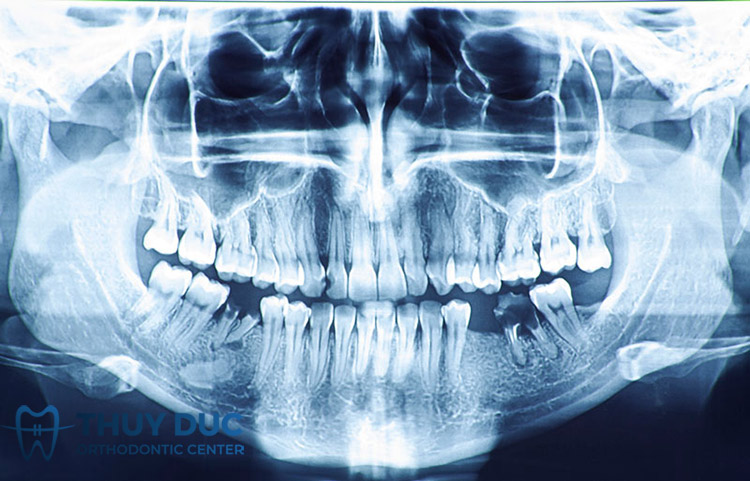

Bước 1: Khám tổng quát và chụp X-quang

Đầu tiên, bác sĩ sẽ khám tổng quát răng miệng của bạn để đánh giá tình trạng sức khỏe của răng, nướu, xương hàm, khớp cắn và thẩm mỹ. Bác sĩ cũng sẽ chụp X-quang hoặc CT-scan để xem xét chi tiết kết cấu xương hàm, độ dày, độ rộng và độ cao của xương hàm, vị trí của các dây thần kinh và mạch máu. Trong bước này, bác sĩ sẽ hỏi thăm tình hình sức khỏe tổng quát, lịch sử bệnh tật, thuốc đang dùng và dị ứng để đảm bảo bạn đủ điều kiện để trồng răng Implant.